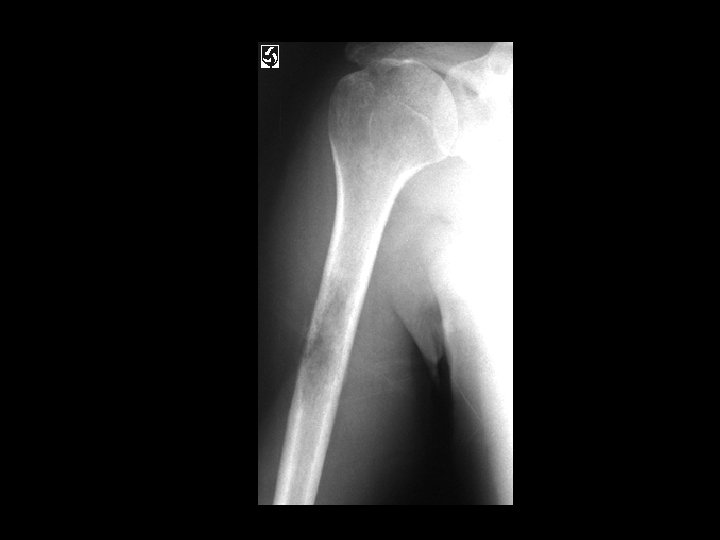

Hill-Sachs Deformity and Osseous Bankart Lesion • • • Findings: – Impaction fracture of the posterolateral humeral margin (Hill -Sachs) – Fracture of the osseous glenoid rim (Bankart) – secondary osteoarthritis Related to repeated anterior dislocations (shoulder instability) Bankart lesion is typically only of the cartilaginous labrum, best seen on MRI